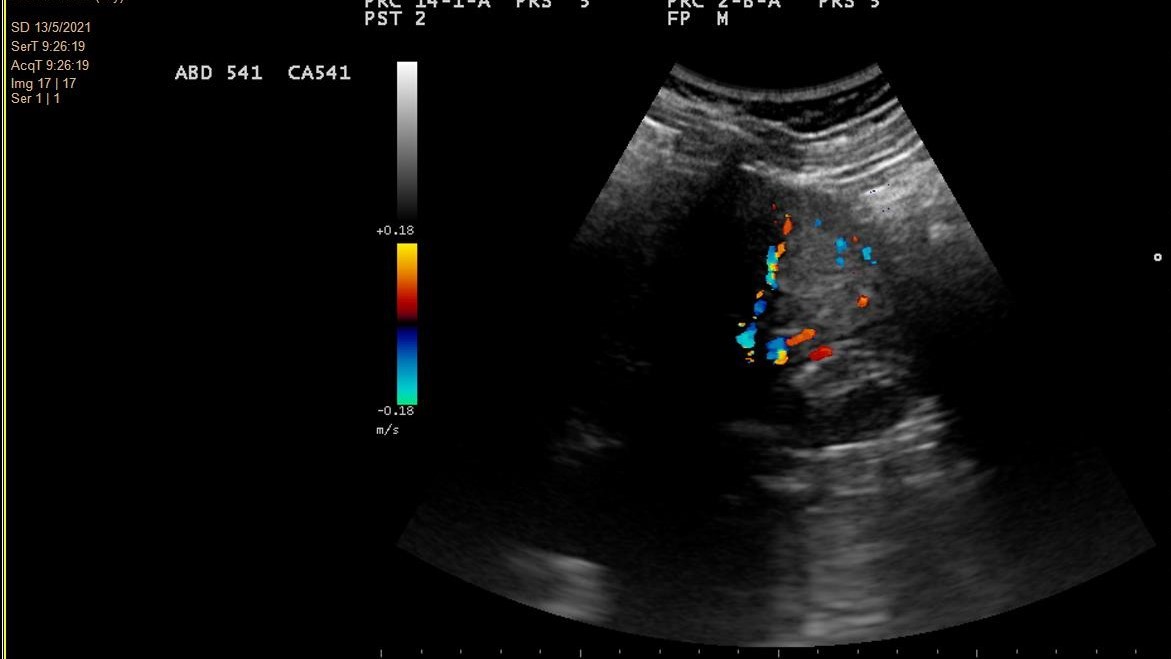

- Hallazgos ecográficos (mayo 2021): Imagen hiperecogénica redondeada de 2,9 cm de diámetro, de ecogenicidad irregular, localizada en tercio medio-distal del riñón derecho, sin evidenciarse litiasis o hidronefrosis.

Juicio clínico: Tumor renal derecho único.